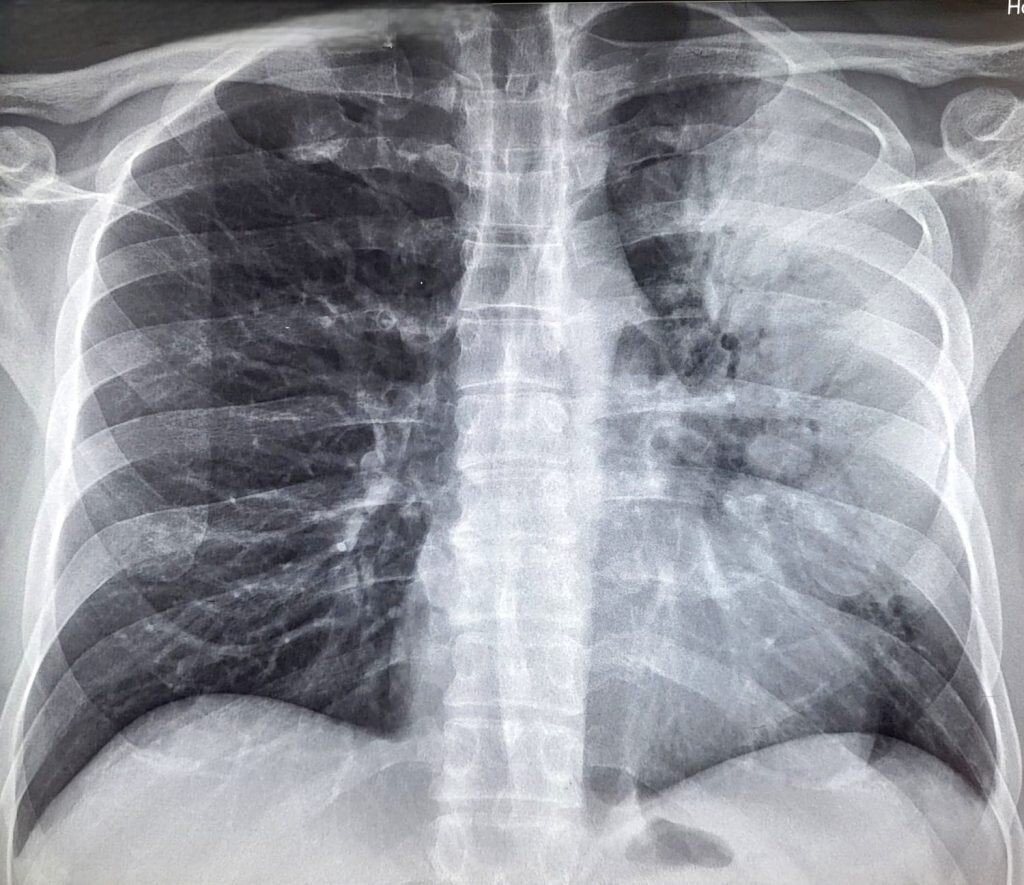

Pneumonia este o boală respiratorie acută care afectează plămânii și care este produsă de agențiinfecțioși. Gripa, virusul sincițial respirator și bacteriile pneumococice sunt cauze frecvente ale pneumoniei, care este determinată în general de microorganisme precum bacterii, viruși și fungi. Simptomele cele maifrecvente ale pneumoniei sunt: febră, frisoane, tuse cu producere de spută, dureri toracice, transpirațieexcesivă, dificultatea în respiraţie (dispnee), starea de oboseală și scăderea poftei de mâncare.